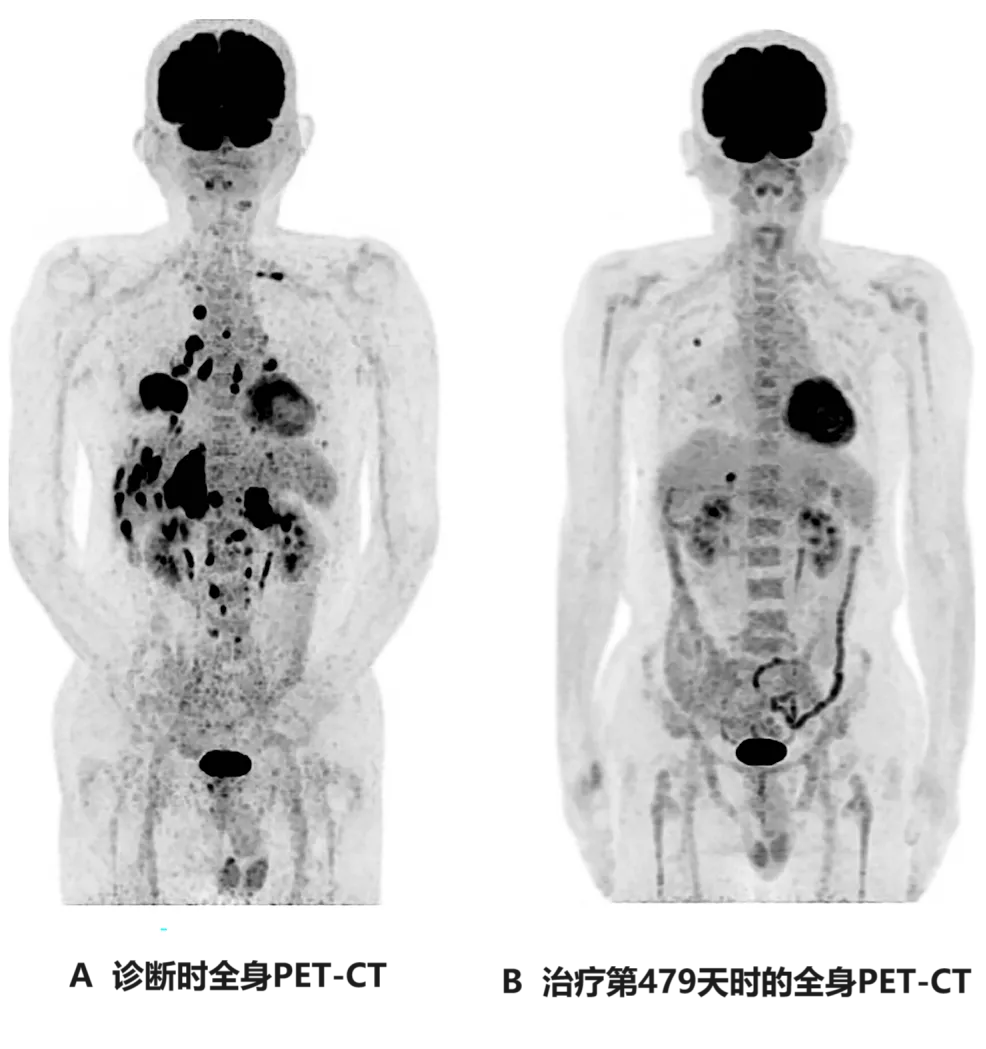

《Cureus》报道了一个“伴全身转移的终末期肺癌患者,经WT1-DC联合二线化疗后,获得长期显著缓解”的案例。本例患者为一名69岁的男性,确诊为右肺中叶IV期鳞状细胞癌,且伴双侧肾上腺转移、多发性骨转移、肝转移,此时已无法耐受手术及放疗等传统治法。入组接受WT1-DC+联合化疗(卡铂AUC6+紫杉醇)治疗后,结果显示如下:

1、无进展生存期(PFS):截至数据统计时止,该患者无进展生存期(PFS)已超577天。

2、癌胚抗原(CEA):癌胚抗原从诊断时的66.4,下降至3.0(治疗第121天)。

3、胸部CT显示:该患者在治疗第114天,复查胸部CT显示,肿瘤明显缩小(详见图2)。

图2  治疗前后胸部CT图像对比

注:

①图A示:原发性右下肺癌,同时伴左右胸腔积液。

②图B示:原发病灶几乎消失。

③图C示:原发病灶存在一定程度的复发。

④图D示:原发性及复发性病灶均缩小。

4、全身PET-CT:治疗后第479天,复查全身PET-CT显示,除肝脏转移灶(直径1.7cm)、右肺转移灶(直径1.0cm)外,未见其他异常表现(详见下图)。

图3  该患者治疗前后全身PET-CT对比

图A:示右下肺原发肿瘤,伴多发性肝转移、多发性双侧肺内转移、多发性骨转移、双侧肾上腺转移。

图B:示肝脏可见1个小转移灶(直径约1.7cm),右肺见2个小转移灶(直径约1.0cm)。

上述结果表明,WT1-DC显著改善了患者的免疫状况,同时有助于维持长期的化疗效果,该例患者经WT1-DC联合辅助化疗后,癌症显著缩小,且幸运的未见复发及转移。